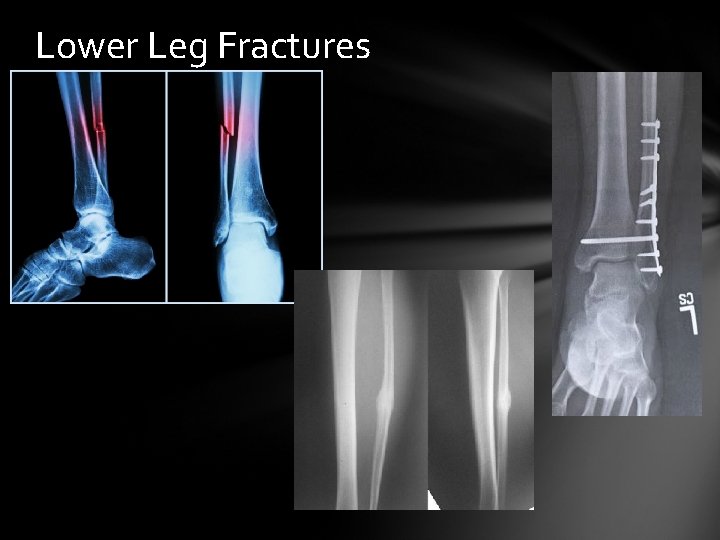

Tibial Fracture & Fibular Fracture Cause: Trauma combined with rotary forces

Lower Leg Fracture Signs & Symptoms: Pain, Swelling, Deformity, Check Circulation, & motion Care: Splint, Transport for medical care. The type of fracture determines whether it is casted or fixed with surgery

Lower Leg Fractures